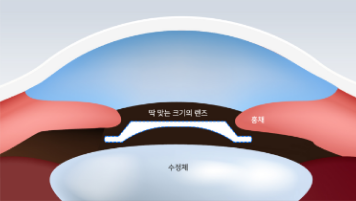

딱 맞는 크기의 렌즈

-

수평으로 렌즈를 삽입할 경우 렌즈 움직임을 최소화하기 위해 눈 보다 큰 사이즈의 렌즈를 삽입하게 되는데 이는 안압 상승의 문제점과 백내장과 녹내장과 같은 치명적인 부작용이 발생할 수 있습니다.

V-토릭 ICL은 여유 공간이 충분한 수직 직경에 맞춘 수술을 위해 특수 제작된 렌즈를 삽입하여 렌즈 사이즈를 최적화하고 안압 상승, 내피세포 손상을 예방할 수 있습니다.

딱 맞는 크기의 렌즈